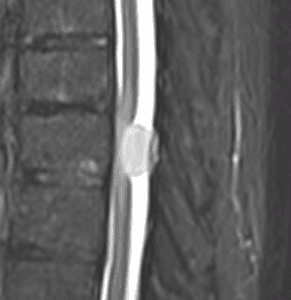

Schwannoma cervico dorsal premedular

Masculino, 66.

Dolor tipo puntada dorsal, interescapular y precordial.

Comenzó a caerse arrodillado de manera espontánea.